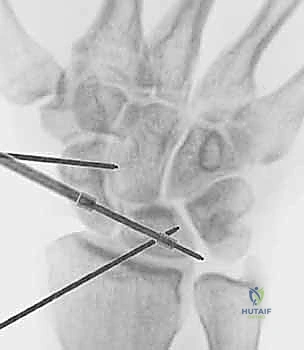

- Technique (Scapholunate Pinning):

- Reduction: First, we must achieve an anatomical reduction of the scapholunate interval. This is often accomplished by direct manual pressure on the scaphoid tubercle and lunate, or by using a small probe to manipulate the bones into alignment. We'll confirm reduction with fluoroscopy.

- Pin Placement: We typically use two 0.045-inch Kirschner wires. The first K-wire is usually inserted from the scaphoid, across the scapholunate joint, into the lunate. The entry point on the scaphoid is typically on its dorsal-radial aspect.

- Fluoroscopic Guidance: This step is absolutely critical. We'll use the mini C-arm to guide the K-wire placement. We need to ensure the wire is:

- Intra-articular: Crossing the scapholunate joint without violating the radioscaphoid or capitolunate joint.

- Central in the bones: Avoiding the edges to prevent breakage and maximize purchase.

- Parallel: The two wires should be parallel to each other, approximately 2-3 mm apart.

- Adequate Length: Sufficiently long to engage both the scaphoid and lunate without protruding excessively.

- Second Pin: A second K-wire is placed in a similar fashion for rotational stability.

- Pin Bending and Capping: Once satisfied with the position on fluoroscopy, the K-wires are cut and bent outside the skin, then capped to prevent migration and skin irritation.

FIG 5 • A. Percutaneous pinning of the scapholunate joint using two K-wires.

FIG 5 • B. Fluoroscopic image confirming satisfactory K-wire placement.